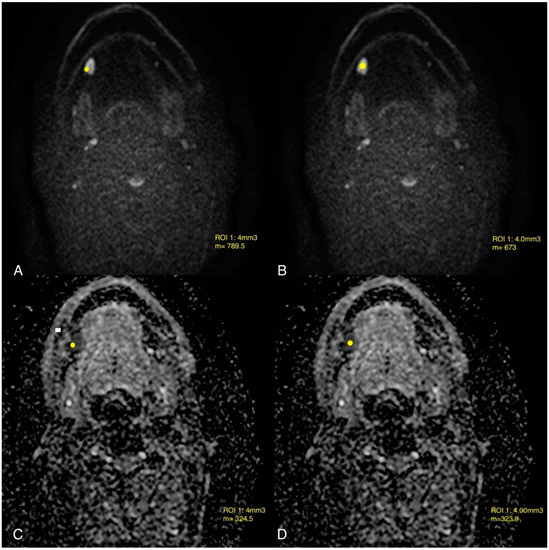

- Jović, A.; Fila, J.; Gršić, K.; Ivkić, M.; Ozretić, D. Diffusion-weighted MRI: Impact of the size of the ROI in detecting metastases in subcentimeter lymph nodes in head and neck squamous cell carcinoma. Neuroradiology 2020, 62, 987–994. [Google Scholar] [CrossRef] [PubMed]